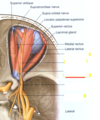

What are these nerves and their function?